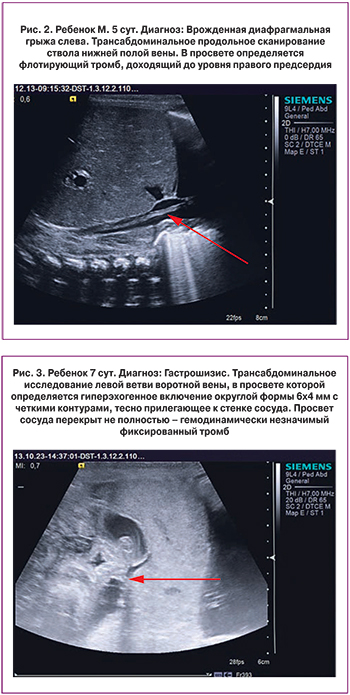

Тромбозы были диагностированы в 14 случаях. Таким образом, частота тромботических осложнений составила 1,4% (14/971), что может быть объяснено сочетанием у новорожденных пациентов перинатальных и хирургических факторов риска для реализации тромботических осложнений. Чаще тромботические осложнения развивались у лиц кавказской национальности; у мальчиков чаще, чем у девочек. Тромботические осложнения во всех случаях были комбинированными. Катетер-ассоциированные тромбозы составили 9/14 случаев тромботических осложнений. Следует отметить, что локализация центрального венозного катетера не влияла на частоту развития тромботического осложнения. Диагноз тромбоза во всех случаях был установлен методом ультразвуковой диагностики (11/14 случаев), в редких случаях тромботические осложнения первоначально имели клинические проявления (2/11 случаев) в виде отечности, изменения цвета и понижения температуры тела пораженного участка ниже тромбоза. Чаще такие случаи сопровождались наличием тромбозов другой локализации. Постановка диагноза тромбоза как находки ультразвукового исследования имела место в 9 из 11 случаев – рис. 1, рис. 2, рис. 3. Интраоперационно диагноз тромбоза был установлен в 3/14 случаев.

В отделении хирургии новорожденных отдела неонатологии и педиатрии ФГБУ НЦАГиП им. В.И. Кулакова Минздрава России с 2010 по 2015 гг. был прооперирован 971 новорожденный ребенок с врожденными пороками развития, потребовавшими проведения раннего хирургического вмешательства, из 1112 поступивших пациентов. Новорожденные с тромбозами в послеоперационном периоде наблюдались по поводу следующих врожденных пороков развития: врожденная диафрагмальная грыжа, гастрошизис, врожденная патология желудочно-кишечного тракта. Тромботические осложнения развивались у новорожденных, находившихся в крайне тяжелом и тяжелом состоянии, потребовавшем проведения дополнительных инвазивных манипуляций. Тромбозы были диагностированы на ультразвуковом аппарате экспертного класса SIEMENS ACUSON S2000 в В-режиме и режиме ЦДК, линейными датчиками с частотой 7–14 МГц и 16–20 МГц. Все случаи тромботических осложнений были диагностированы ультразвуковыми методами исследования, за исключением 3/14 случаев, когда тромбоз был подтвержден интраоперационно.